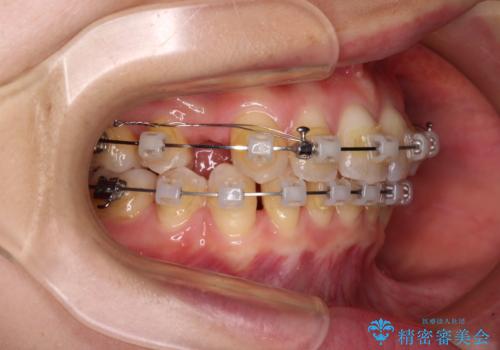

- クリアブラケット

骨格的な左右差と、歯列から外れている歯が上下で左右非対称になっていることから、上下正中が歯1本分ずれている状態でした。

八重歯の改善と、上下の正中位置を極力合わせていくことを目的として、上下左右の第一小臼歯4本を抜歯し、ワイヤー装置にて矯正治療を行うこととしました。

アンカースクリューを用いて正中位置を調整したことで、上下の正中位置をほぼ一致させることができました。